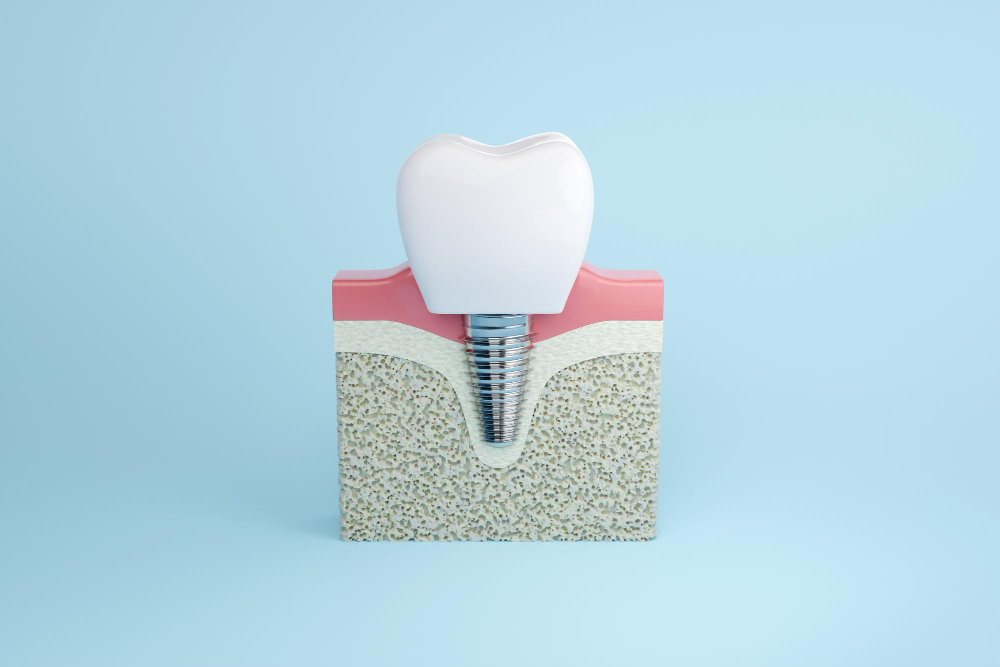

What Are Dental Implants? Dental implants are artificial tooth roots. Dentists place them into your jawbone to support replacement teeth. Usually, they are made of